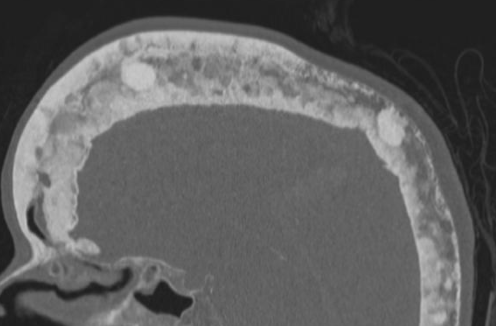

Cotton Wool Skull

- Patchs de sclérose dans un crane lytique

- Risques d’atteinte neurologique à la base du crâne

- Epaississement des corticales et trabéculaire

Risque de transformation en sarcome

- Fractures pathologiques avec régions de lyse exagerée

- RX: régions de Lyses progressive

- IRM: Remplacement médullaire